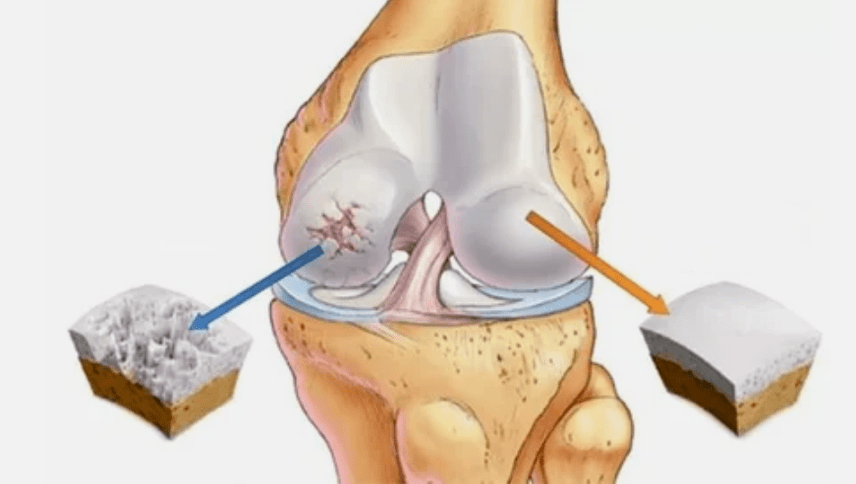

- De primaire laesie beïnvloedt het hyalinekraakbeen. In het geval van bloedsomloop treedt de achteruitgang van pathologische kracht op. Het is de eerste stap of oorzaak, die artrose kan optreden.

- Hyalin -coatingpathologieën. Het dunner worden van het kraakbeen leidt tot de vervanging van zijn pathologische weefsels - botstructuren.

- Afwijkende gezwellen verschijnen op kraakbeen - osteofyten.

- De ontstaande schending van de natuurlijke anatomie van het kraakbeen en botten veroorzaakt de overbelasting van gezonde gebieden van kraakbeen. De vernietiging van articulaire weefsels zonder behandeling gaat constant vordert en leidt tot handicap.